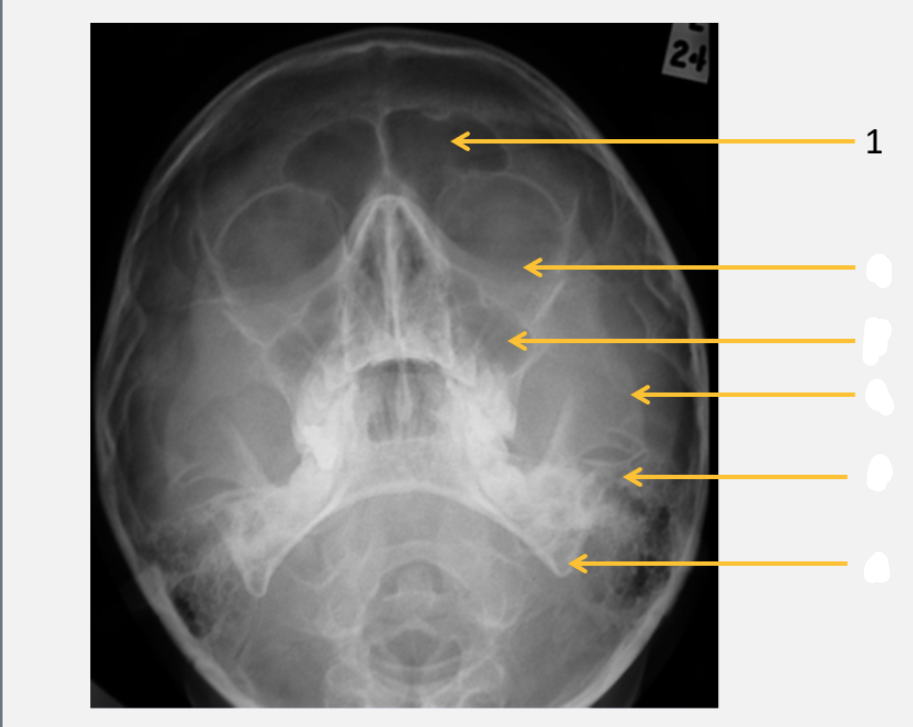

frontal sinus

inferior orbital rim

maxillary sinus

zygomatic arch

petrous ridge

angle of mandible